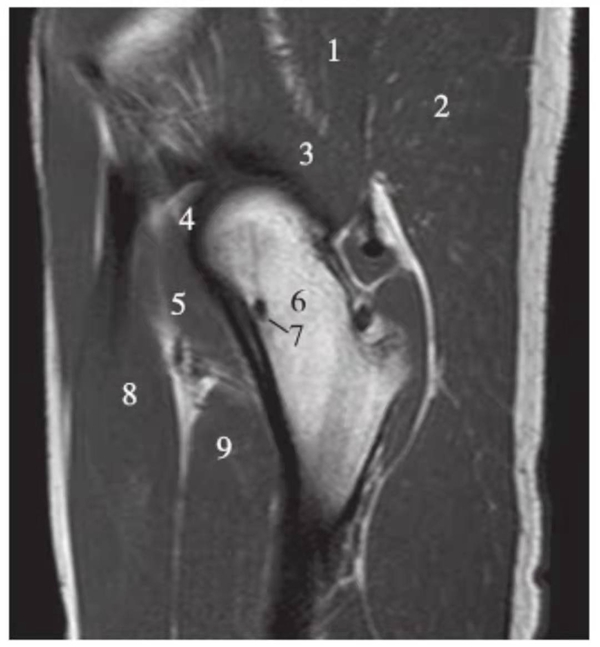

矢状位

正常髋关节经股骨头内缘层面T1WI像

1.髂骨;2.臀大肌;3.圆韧带;4.股骨头;5.坐骨;6.闭孔外肌;7.耻骨肌;8.大收肌